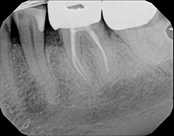

Non-surgical root canal treatment:

Before

Immediately After

6-month follow-upThis patient presented with pain when chewing. Diagnostic testing was done and determined it was the lower molar. The diagnosis was: pulpal necrosis, symptomatic periradicular periodontitis. Root canal treatment was performed with laser disinfection. The tooth had a crown and we accessed the tooth through the crown. We saved the tooth and the crown.